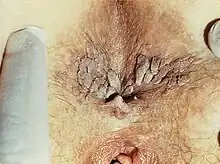

| Genital warts | |

| Severe case of genital warts around the anus of a female | |